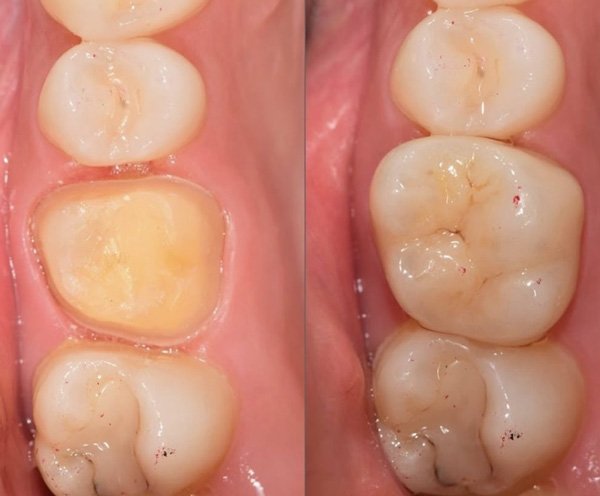

Recuperação de dentes danificados por cárie, fraturas ou desgaste, devolvendo função, estética e saúde bucal com restaurações modernas e duráveis.